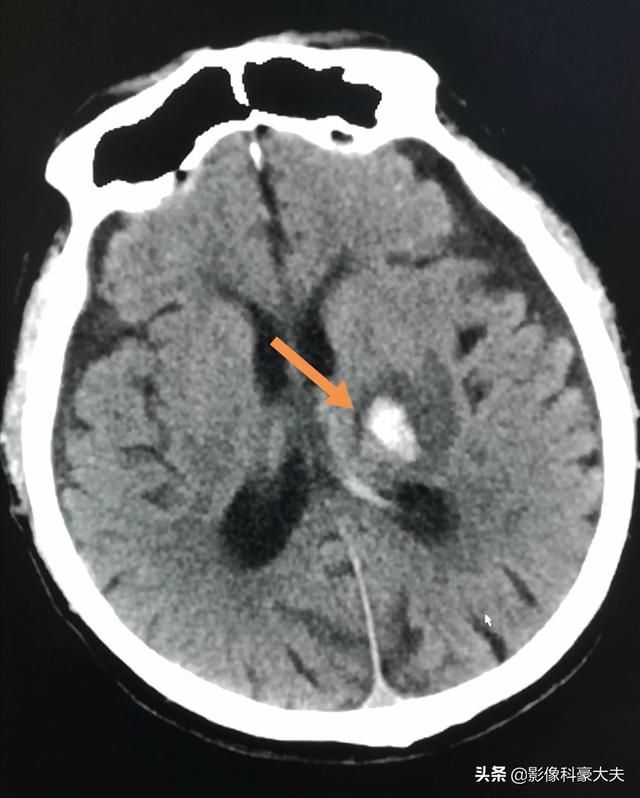

Ce patient, âgé de 52 ans, a été admis pour des maux de tête soudains et un scanner a clairement montré une hémorragie cérébrale thalamique gauche. Cette petite hémorragie est généralement mieux traitée et ne laisse pas de séquelles graves.

Plus de la moitié des hémorragies intracérébrales sont causées par l'hypertension artérielle, c'est pourquoi nous disons souvent que nous devons prendre des médicaments contre l'hypertension artérielle, même en l'absence de symptômes, par crainte d'une hémorragie cérébrale soudaine, et en prenant des médicaments pour contrôler la tension artérielle au bon niveau, nous pouvons réduire considérablement le risque d'hémorragie cérébrale. Les autres causes d'hémorragie intracérébrale sont les anévrismes, les malformations vasculaires cérébrales, les accidents vasculaires cérébraux dus à des tumeurs cérébrales et les complications d'un traitement anticoagulant. L'hémorragie intracérébrale peut être associée à de violents maux de tête, à des vomissements et à l'apparition précoce de symptômes neurologiques tels que l'hémiparésie, les troubles de la parole et l'épilepsie (c'est-à-dire que la personne entière ne réagit pas). Les hémorragies du tronc cérébral et du cervelet peuvent également se manifester par des vertiges. La photo ci-dessous montre un patient souffrant d'une hémorragie intracérébrale (zone blanche sur la photo ci-dessous), ayant des antécédents d'hypertension, qui s'est soudainement effondré alors qu'il faisait du vélo dans la rue.